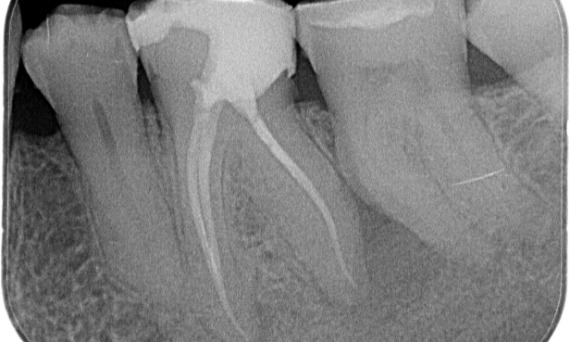

Before: Periapical radiolucency associated primarily with the distal root and loss of lamina dura on the mesial root.

After: TruNatomy was chosen in this case to allow a caries leveraged approach and a focus on pericervical dentin preservation especially on the mesial aspect where the tooth had a more minimal restoration.

Bath, UK